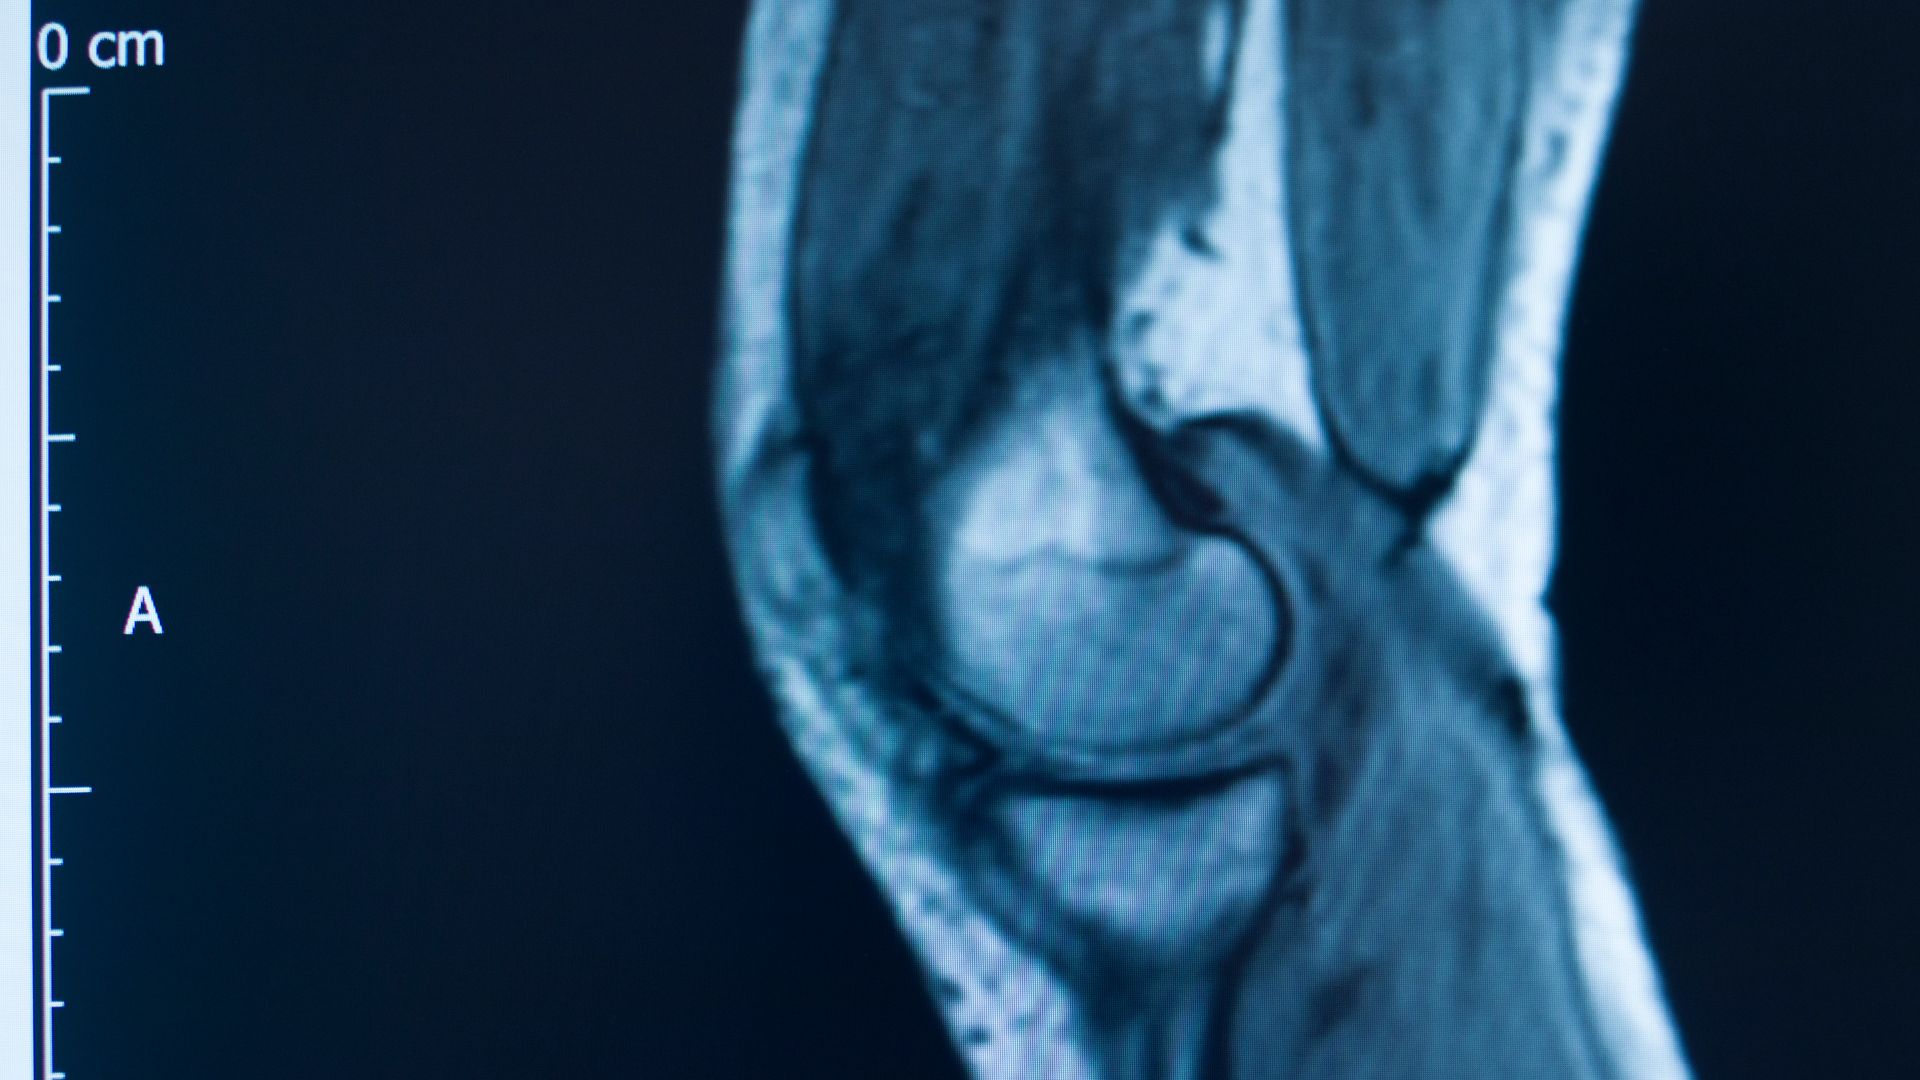

El Sr. Martín llegó a consulta tras sufrir una lesión severa en la rodilla mientras realizaba tareas de carga y descarga en su trabajo. La evaluación inicial reveló una rotura del ligamento cruzado anterior (LCA) y una lesión en el menisco, lo que le impedía caminar sin dolor.

Dada la gravedad del caso, se optó por una cirugía de reconstrucción ligamentaria.

El procedimiento consistió en la colocación de un injerto tendinoso para reemplazar el ligamento dañado, junto con una reparación del menisco. La cirugía fue un éxito y permitió que Martín iniciara su proceso de rehabilitación a los pocos días.